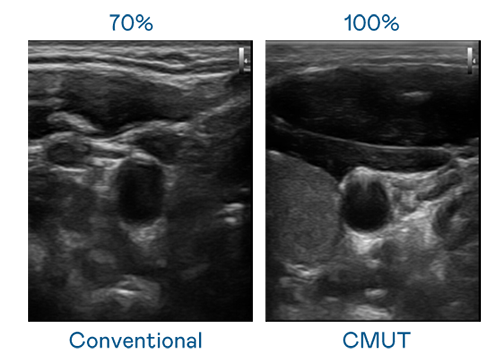

CMUT 技术是一种用电容式微机电元件来产生超音波讯号的技术。与传统 PZT 压电式技术相比,CMUT 频宽增加 30%,更宽频的超音波讯号让影像解析度大幅提升,是实现高影像品质医疗超音波扫描、促进精准医疗发展的关键技术。

大频宽带来超清晰影像

超音波影像的解析度高低,首先取决于探头能发出的讯号频宽。星空体育网页版在线登录官网入口 CMUT 可提供高清晰的超音波讯号,提供高频宽、高灵敏度、影像纹理细节更高的超音波影像,协助医护人员缩短影像判读时间及利用精准的医疗影像进行诊断。